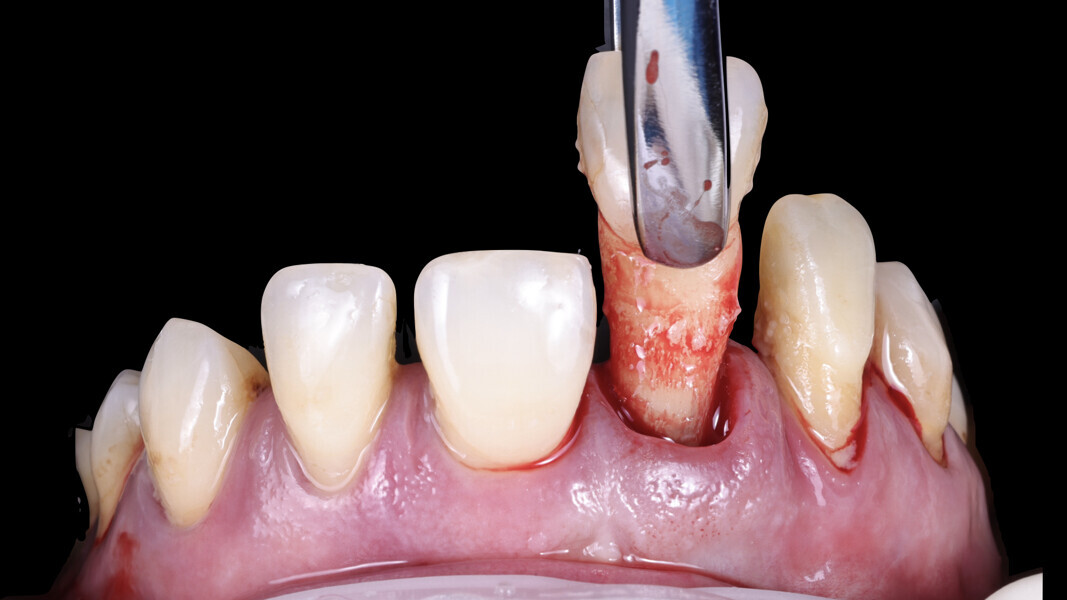

2. Gentle tooth extraction: Selected teeth were carefully extracted with minimal trauma to preserve the buccal and palatal soft tissue as well as the papillae (Figs. 14–16), leaving selected teeth in place to stabilise the surgical guide.

3. Guide verification and fit check: For this case, we opted for a tooth-supported guide, which is highly accurate and straightforward to execute. The guide was verified for proper fit before proceeding.

4. Guided implant placement: Eight implants were placed using a guided approach, achieving optimal progressive torque of 35 N cm and excellent bone–implant contact (Fig. 17).